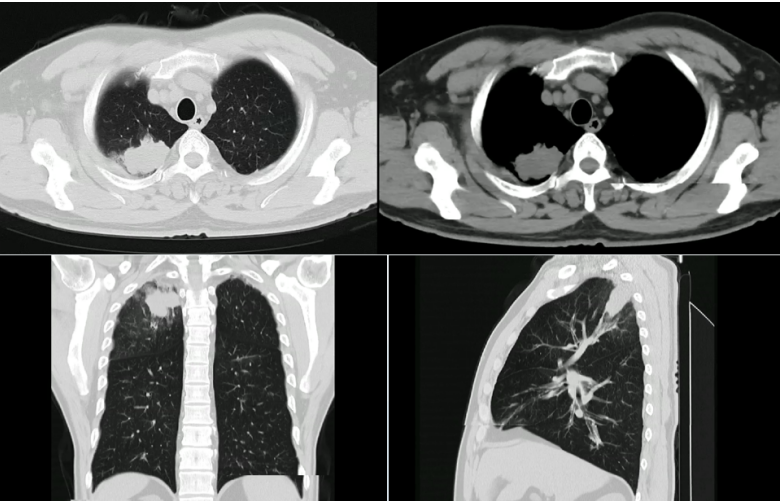

患者2015年12月7日在本院就诊时的胸部CT显示两上肺以及左肺胸膜下均有病变(图6)。追问病史。患者曾接受抗结核治疗一年半。2017年6月13日复查胸部CT显示两上肺病灶基本消失(图6),说明患者曾经感染过结核,并且抗结核治疗有效。

6  患者胸部CT比较

2023年12月11日(服药6周后)复查胸部CT:上肺肿块明显消退,仅残存一些小的纤维灶,额状面和矢状面变化明显(图7)

7  患者胸部CT(2023年12月11日)